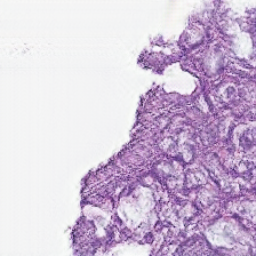

The Figure 3 shows virtual H&E generation from light-sheet microscopy image. Each column represents a different type of image. Each row corresponds to a different slice. From these images, it can be observed that the CycleGAN has learned to map the nuclear and cytoplasmic signals to the characteristic H&E colors. Overall tissue morphology and structure are largely preserved, demonstrating that the model captures the spatial relationships of nuclei and cytoplasm from the fluorescence channels.

| C01 | C02 | virtual H&E images |